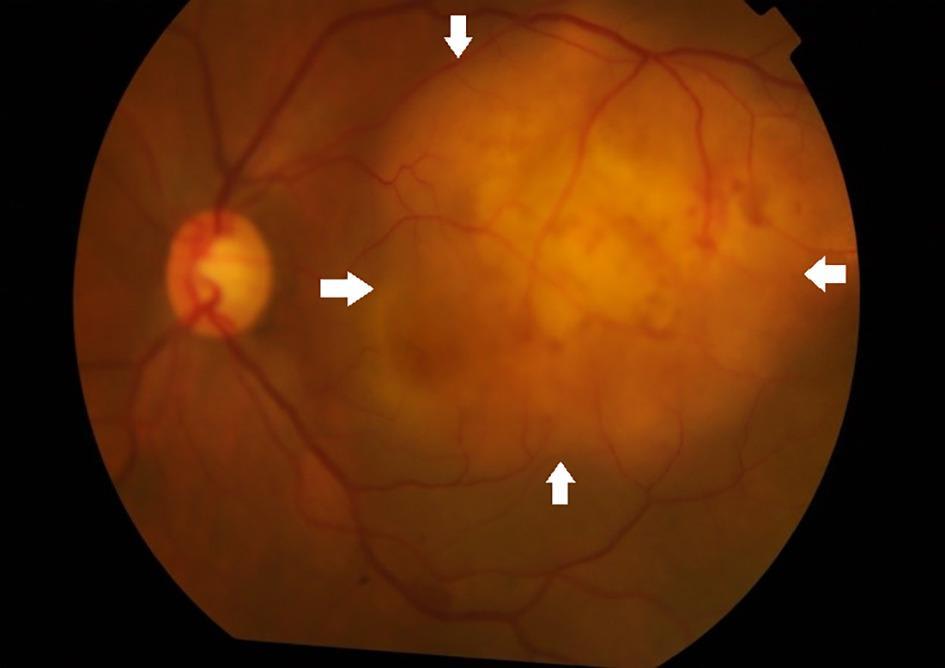

Характерна офтальмоскопічна картина (серпигінозний хоріоїдит — типове хвилеподібне запалення хориоїдеї, що може поступово розповсюджуватися; перифлебіт із оклюзією судин, що свідчить про запальне ураження судинної оболонки ока.

Ціі зміни не є абсолютно специфічними, проте їх наявність у поєднанні з клінічними симптомами підсилює підозру на туберкульозний генез увеїту.

Офтальмоскопічно очне дно демонструє низку типових змін:

Поодинокі або множинні хоріоїдальні гранульоми (туберкульоми);

“Мультифокальні” вогнища хоріоїдиту;

Серпигінозні плями з активним жовтим краєм і пігментованим рубцевим заднім краєм;

Ретинальний васкуліт із “гільзами”, ішемічними ділянками, крововиливами;

Неоваскуляризація диска або периферії;

Преретинальні фіброзні тяжі, проліферативні зміни.